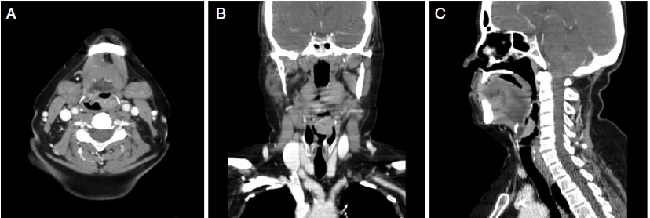

An incisional biopsy revealed that the lesion was a moderately differentiated squamous cell carcinoma (SCC). Assessment by computed tomography (Fig. 1) showed that the lesion had limits compatible with the laryngoscopy, without pre-epiglottic space involvement and without cervical lymph nodes suggestive of metastases. There was no evidence of pulmonary metastases; the search for a second primary tumor through high digestive endoscopy with chromoendoscopy was negative, and the cancer was staged as T2N0M0 (stage II).